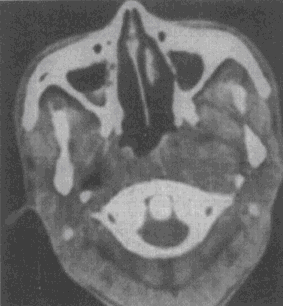

1.男性,50岁。涕中带血丝1个月余,无发热及咽部肿痛。CT检查见图所示,应首先怀疑以下何种疾病

A.鼻咽癌

B.咽旁脓肿

C.咽部淋巴结炎

D.喉癌

E.神经纤维瘤

正确答案:A解题思路:鼻咽癌病理上主要包括鳞状细胞癌、腺癌、泡状细胞癌和未分化癌。按其发展方向可分为上行型、下行型和混合型。